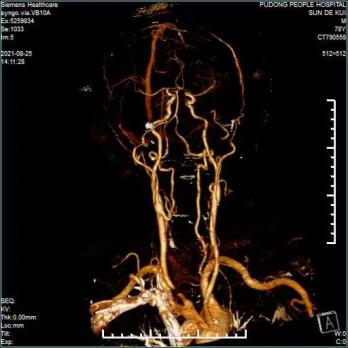

术前椎动脉CTA未见椎动脉高跨表现手术方法主要以前路齿状突螺钉加压内固定术和后路内固定手术为主:前路齿状突螺钉加压内固定术相对安全,但螺钉固定强度及复位能力不足;后路内固定手术方式相对安全的有椎板夹内固定、钢丝内固定等,但同样固定强度不佳,骨折端不融合发生几率高,枕颈融合术相对固定强度较大,但颈椎活动度受到限制,患者远期效果并不理想。为让患者术后保留更多的颈椎活动范围,手术团队放弃了风险相对较低的枕-颈融合术,而采用手术技术要求极高的寰-枢椎椎弓根钉内固定手术。在决定了治疗方案后,脊柱外科团队对患者进行了一系列术前准备工作,包括颈椎MRI检查、椎动脉CTA明确有无椎动脉解剖变异等。